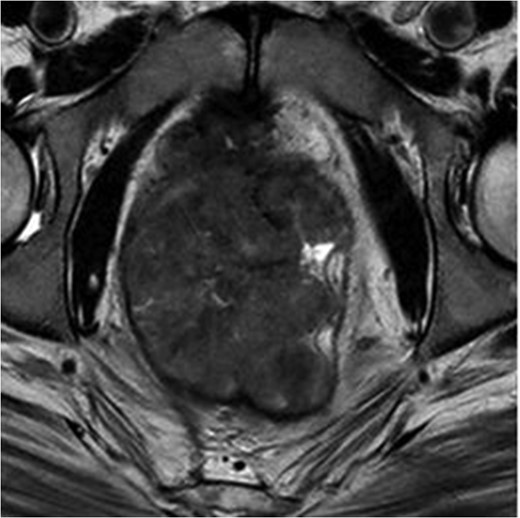

MRI pelvis. T2 waited axial image through lower pelvis through the large polypoid rectal tumour with T3 extension involving the CRM.